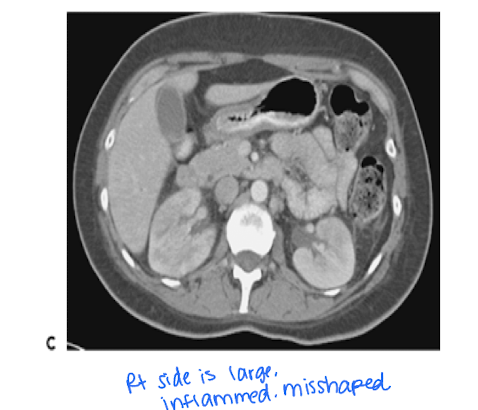

When is imaging indicated in a patient with pyelonephritis?

pyelonephritis is a severe urinary tract obstruction when there is suspicion of abscess, obstruction, or complications.

An infection that can be difficult to dx on CT if patient is not responsive to treatment

After a renal mass is detected, what is the next logical step?

Further imaging including CT